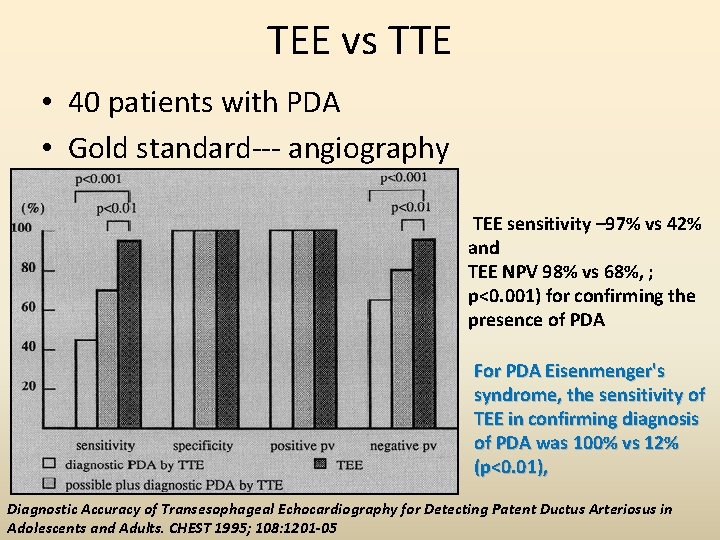

TEE vs TTE • 40 patients with PDA • Gold standard--- angiography TEE sensitivity – 97% vs 42% and TEE NPV 98% vs 68%, ; p<0. 001) for confirming the presence of PDA For PDA Eisenmenger's syndrome, the sensitivity of TEE in confirming diagnosis of PDA was 100% vs 12% (p<0. 01), Diagnostic Accuracy of Transesophageal Echocardiography for Detecting Patent Ductus Arteriosus in Adolescents and Adults. CHEST 1995; 108: 1201 -05